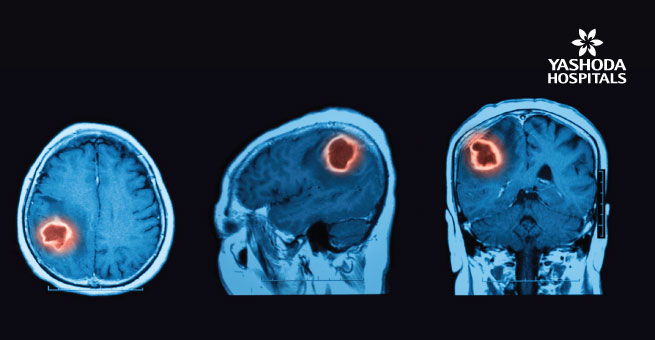

A brain tumor is a tumor which develops in the cells of the brain. A growth, collection or mass of abnormal cells in the brain is called a brain tumor. These tumors can occur at any age.

It can be either noncancerous (benign) or cancerous (malignant) and vary greatly based on their location. The location of the tumor determines the effect on the central nervous system (CNS) along with their symptoms and growth rate. When benign or malignant tumors grow, they can cause the pressure inside your skull to increase, this can lead to brain damage and can be life- threatening. Brain tumor treatment options depend on the type of brain tumor one has along with its size and location.